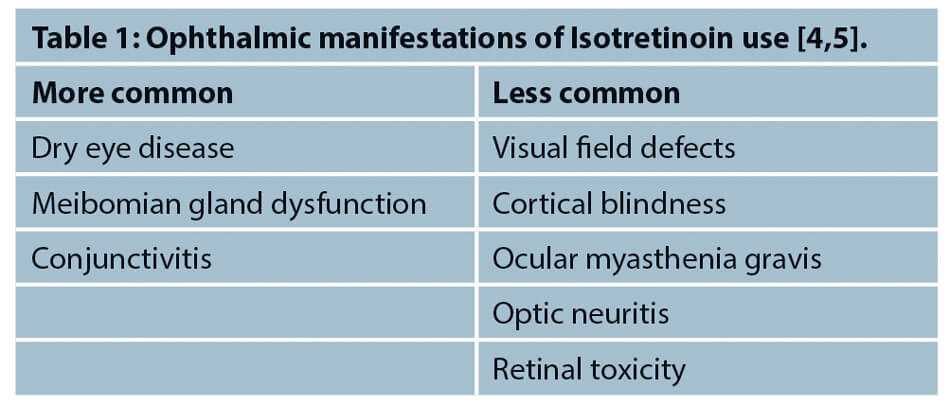

Isotretinoin (13-cis-retinoic acid) is the first line treatment for moderate to severe nodulocystic or papulopustular acne [1,2]. Although it is a safe medication, it has several adverse side-effects, including ophthalmic manifestations, as shown in Table 1 [3]. These side-effects need to be recognised early, treated and / or referred to an ophthalmologist, to prevent significant ocular morbidity.